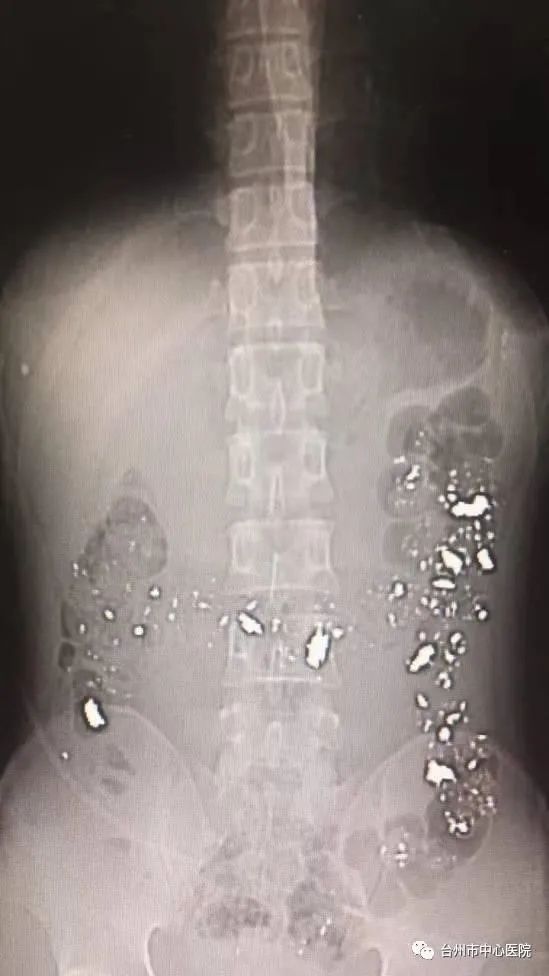

据杭州日报报道,2017年,浙江台州一位小伙子食铅能强身健体,而且得知古代炼丹原料,主要是铅和汞。于是,决定通过服食铅粉来让自己脱离“亚健康"状态。

结果身体内过量的铅,让他“头疼恶心”,让造血功能出问题,导致严重贫血,面色苍白,而且连肝脏也出现了损伤。

腹部CT片

为其接诊的医生表示:“铅中毒对血液系统、肝脏系统和神经系统的损害最为严重,会造成白血病、脏器功能衰竭等严重后果。”⑪